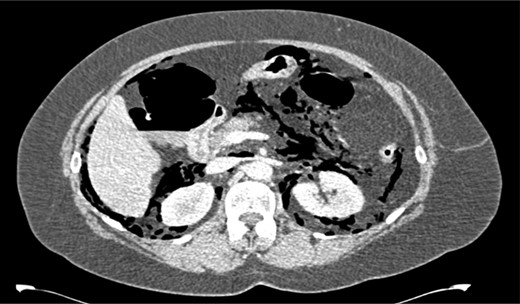

After her procedure she complained of swelling in her neck. This was not accompanied by shortness of breath, chest pain or abdominal pain. On examination, her oxygen saturation was 99% on room air, with normal respiratory and heart rate. Her respiratory examination was normal and her abdomen was soft and non-tender. She had marked crepitus over her clavicles, supraclavicular fossa and most of her neck. Her erect chest X-ray revealed air under both hemidiaphragms and significant pneumomediastinum (Fig. 1). A computed tomography (CT) scan of her chest, abdomen and pelvis was requested. This CT-scan revealed very extensive spreading of surgical emphysema in the retroperitoneum, extending into the mediastinum with small volumes of free intraperitoneal gas (Figs 2–4).

CT scan of abdomen showing free intraperitoneal gas compressing the splenic flexure.